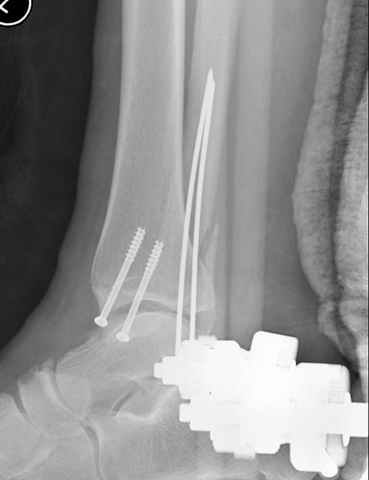

Второй случай сделан из одного разреза

ЕЧ LISS plate, mininvasive approach - luxurous !

Вопрос практического характера - такой подход рутинный или при определенных показаниях и каких? Спрашиваю потому, что при потоке больных - закрытая голень, бедро, голеностоп и т.д. лучевая нагрузка должна быть немалая, каковы показатели дозиметра после такого операционного дня и при 2-3 операционных днях в неделю по 5-6 случаев (не считая ургентностей)?

С точки зрения : Сгорая сам - свети другим :-)) это вполне понятно, но личная практика показывает, что далеко не все пациенты относятся волнительно и критично к длине кожного разреза. Подозреваю, что это и есть критерий при выборе техники фиксации?

На прямой проекции послеоперационного Рг макроскопически все выглядит очень анатомично, при микроскопическом ( :-)) ) рассмотрении можно все-таки заметить вальгизацию тарана, суставная щель в латеральном отделе сустава несколько уже , чем в медиальном при отсутствии латерального смещения тарана. У меня был аналогичный случай (без LISS , без мини доступа) с вальгусным наклоном тарана при восстановленном ankle mortise при последовательном наблюдении с интервалами в 6-8 недель в послеоперационном периоде отмечалось прогрессирующее сужение суставной щели в латеральном отделе сустава, закончившееся посттравматическим ОА, к счастью боли умеренные, купируемые аналгетиками или своими эндорфинами:-))(активная пациентка, у которой нет времени на болезни....) Какова жизненная ситуация в приведенном вами случае? И последнее, что я хотел бы прояснить для себя - фиксация внутренней лодыжки: я обычно комбинирую фиксацию компрессирующим винтом со спицей - по идее ротационная стабильность должна быть лучше, чем один винт, каковы ваши наблюдения в этом плане?